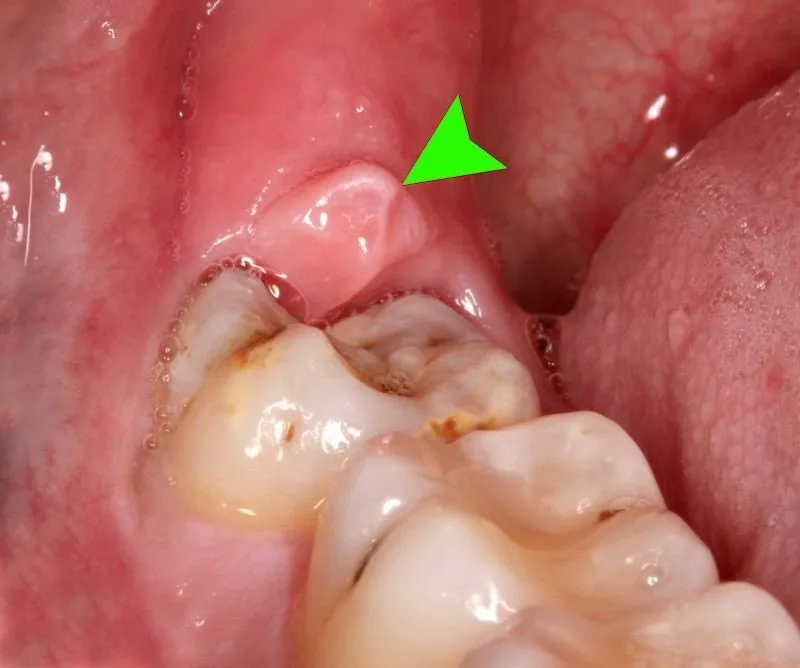

Hình ảnh viêm lợi trùm

Để giúp các bạn biết rõ bênh viêm lợi trùm, Nha khoa DrGreen xin gửi tới các bạn hình ảnh viêm lợi trùm chi tiết. Thông qua đó các bạn có thể nắm rõ và điều trị kịp thời. Cụ thể như sau:

Trên đây là những hình ảnh viêm lợi trùm rõ nhất mà bạn cần biết. Cùng với đó là nguyên nhân và cách điều trị hiệu quả bệnh này. Để được tư vấn cụ thể, hãy liên hệ Nha khoa DrGreen theo thông tin bên dưới